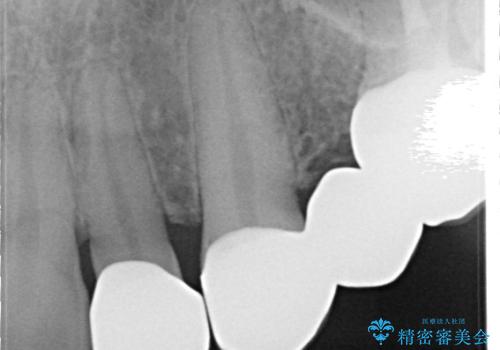

- 昔装着したかぶせ物が、不自然なのでやりかえたいとのことで来院されました。

前歯にレジン前装冠(保険内)が装着されており、自然な透明感がありません。

また奥歯にまたがるブリッジも金属のもので、適合もよくありませんでした。